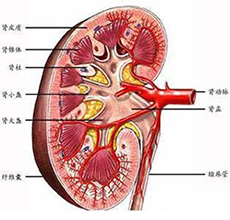

急性肾衰竭(ARF)

疾病介绍:急性肾衰竭(ARF)是指肾小球滤过功能在数小时至数周内迅速降低而引起的以水、电解质和酸碱平衡失调以及氮质代谢产物蓄积为主要特征的一组临床综合症,…【详细】